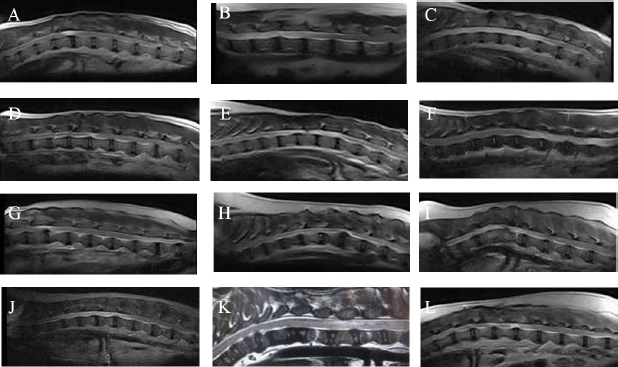

CT scans confirmed previous surgical interventions in the thoracolumbar region (T11–L3) in all animals. T2-weighted MRI scan confirmed signal hyperintensity in all cases. In six animals (Cases 2, 3, 5, 6, 9, and 10), T2-weighted signal hyperintensity was extensively observed along more than three vertebral bodies (Fig. 1).

Fig. 1. T2-weighted MRI images. (A): Case 1. (B): Case 2. (C): Case 3. (D): Case 4. (E): Case 5. (F): Case 6. (G): Case 7. (H): Case 8. (I): Case 9. (J): Case 10. (K): Case 11. (L): Case 12.